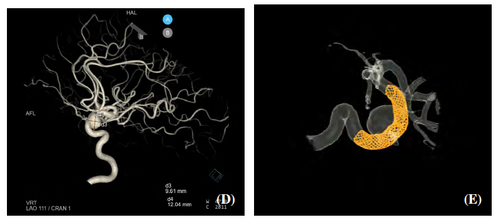

V rámci společného projektu proof-of-concept byl analyzován případ pacientky s aneurysmatem na jedné z hlavních mozkových tepen. Výpočetní dynamika tekutin (CFD) zde sloužila jako podpůrný nástroj, který v realistickém 3D modelu cév vytvořeném z angiografických dat umožnil kvantifikovat parametry, jako jsou smykové napětí, oscilace toku nebo doba setrvání krve. Na základě výpočtů bylo možné porovnat vybrané hemodynamické charakteristiky před a po zákroku.

Simulace byly realizovány na superpočítači Karolina, který provozuje IT4Innovations národní superpočítačové centrum. Odborníci z Laboratoře vývoje paralelních algoritmů zajišťovali metodiku, softwarové řešení, analýzu i vizualizaci. Výsledky přinesly detailnější pohled na to, jak léčba ovlivnila hemodynamiku v oblasti aneurysmatu, a poskytly klinickému týmu další kvantitativní podklady pro interpretaci nálezu.

CT snímky aneurysmatu u sledované pacientky